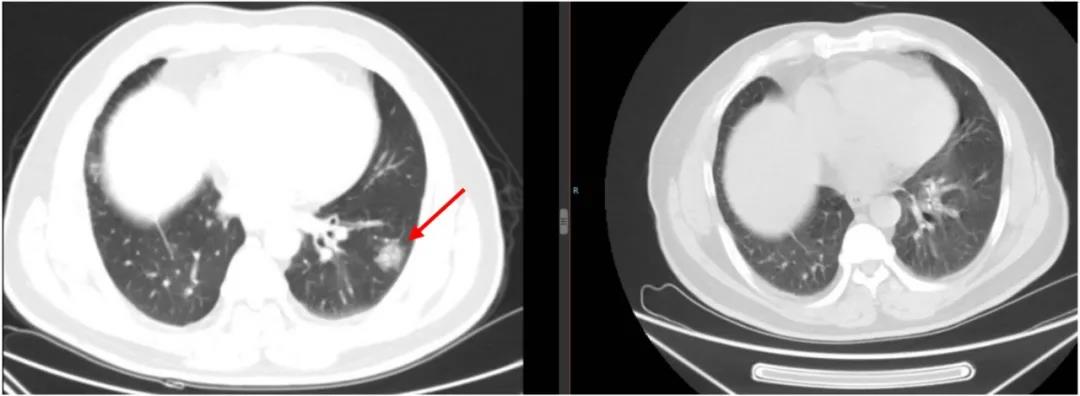

2018年3月13日门诊复查CT证实疾病复发(双肺下叶多发结节影,左肺下叶病灶较大,直径约1.7cm)。

结合指南推荐与患者实际情况,一线治疗方案选择重组人血管内皮抑制素联合长春瑞滨+顺铂(NP)方案化疗4周期,疗效评价为CR。后续使用重组人血管内皮抑制素单药维持治疗29个周期。